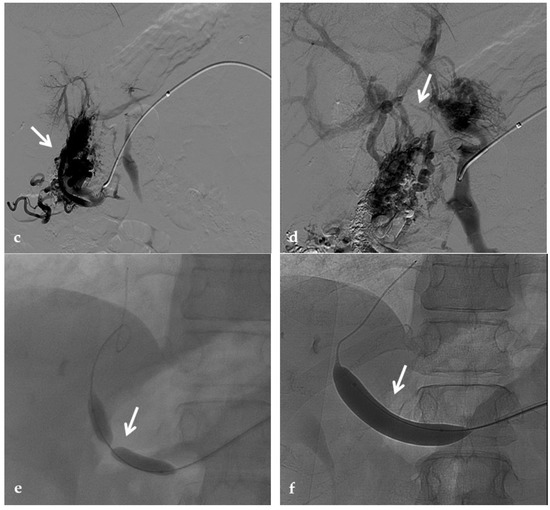

Figure 12.

Anteroposterior view of a percutaneous transhepatic and transsplenic portography imaging series of a chronic complete extrahepatic portal vein thrombosis with portal cavernous transformation in a 17-year-old boy with a history of gastrointestinal bleeding and portal hypertension after liver transplant for biliary atresia. (a) Percutaneous transhepatic portography shows complete extrahepatic portal vein thrombosis (white arrow), with opacification of an irregular cavernomatous network (black arrow). (b) Opacification of a very tiny fibrotic cord representing the thrombosed portal trunk is seen (arrow). Several attempts to cross the portal vein occlusion failed. (c) Percutaneous transsplenic anterograde portography shows complete extrahepatic portal vein thrombosis and cavernous transformation (arrow) from a different perspective. (d) The tiny residual of the thrombosed main portal trunk (arrow) was easily recognized on the transsplenic superior mesenteric vein portography. (e) Fluoroscopic image shows angioplasty of the main portal vein, performed through a 12-mm non-compliant balloon catheter. The focal notch (arrow) represents the tight anastomotic stenosis that probably led to secondary thrombosis. (f) Fluoroscopic image shows the resolution of the focal notch (arrow) after high-pressure inflation of the non-compliant 12-mm balloon catheter. (g) Control portography shows an expanded main portal vein with improved hepatopetal portal flow, but still with irregular profiles (arrow). (h) Through a hybrid transhepatic and transjugular approach under combined ultrasound and fluoroscopic guidance, the connection between the intrahepatic portal vein and the vena cava was created advancing a 0.018” micro guidewire into the right atrium (arrow). The wire was snared through the right transjugular access providing a through-and-through access for precise transjugular intrahepatic portosystemic shunt (TIPS) placement. The completely image-guided hybrid approach allowed to reduce the attempts of transjugular intrahepatic portal vein puncture. (i) Portography image shows the deployment of two imbricated Viatorr stents to create the TIPS (arrows), with regular intrastent opacification. Despite previous angioplasty, a prestenotic aspect of the main portal vein is seen (black arrow). (j) Portography image shows a self-expandable 9-mm metallic stent placed to cover the main portal vein trunk stenosis (white arrow). Control portography shows regular mesenteric-portal vein opacification with TIPS patency and preserved opacification of intrahepatic portal branches (black arrows); cavernous vessels disappeared.